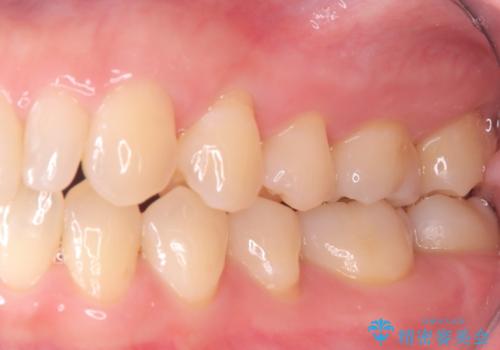

今回は、経年的な劣化が少なく、汚れが付着しにくいセラミックインレーを用いて治療を行いました。

セラミックインレー装着時には、唾液が入らないようラバーダムシートを使用し、接着精度を高めることで、長く安心して使っていただける治療を心がけています。